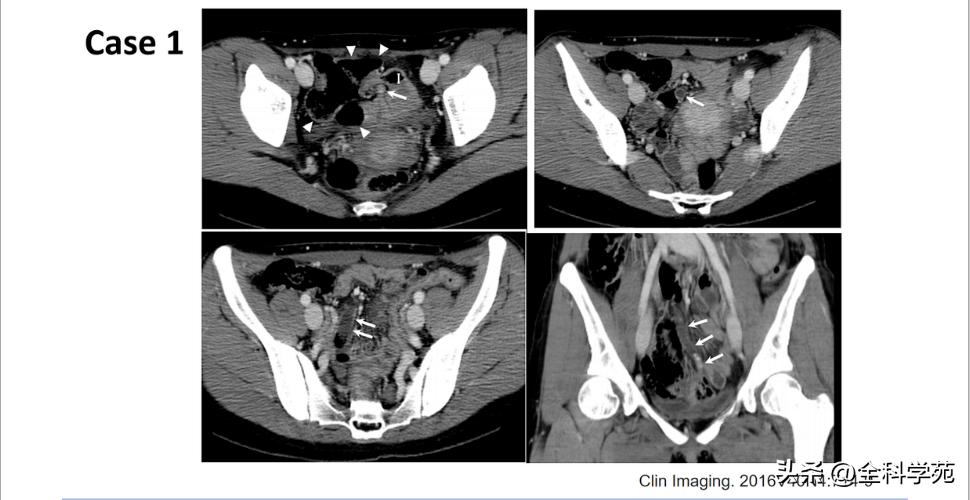

◆ 穿孔 (Perforation)

◆ 局部低强化是穿孔征象

◆ 蜂窝织炎和脓肿 (Phlegmon and abscess